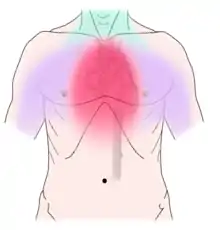

Pulpitis is reversible when the pain is mild to moderate and lasts for a short time after a stimulus (for instance cold); or irreversible when the pain is severe, spontaneous, and lasts a long time after a stimulus. Left untreated, pulpitis may become irreversible, then progress to pulp necrosis (death of the pulp) and apical periodontitis. Abscesses usually cause throbbing pain. The apical abscess usually occurs after pulp necrosis, the pericoronal abscess is usually associated with acute pericoronitis of a lower wisdom tooth, and periodontal abscesses usually represent a complication of chronic periodontitis (gum disease). Less commonly, non-dental conditions can cause toothache, such as maxillary sinusitis, which can cause pain in the upper back teeth, or angina pectoris, which can cause pain in the lower teeth. Correct diagnosis can sometimes be challenging.

Non-dental causes of toothache are much less common as compared with dental causes. In a toothache of neurovascular origin, pain is reported in the teeth in conjunction with a migraine. Local and distant structures (such as ear, brain, carotid artery, or heart) can also refer pain to the teeth.[35]: 80, 81 Other non-dental causes of toothache include myofascial pain (muscle pain) and angina pectoris (which classically refers pain to the lower jaw). Very rarely, toothache can be psychogenic in origin.[10]: 57–58

From the history, indicators of pulpal, periodontal, a combination of both, or non-dental causes can be observed. Periodontal pain is frequently localized to a particular tooth, which is made much worse by biting on the tooth, sudden in onset, and associated with bleeding and pain when brushing. More than one factor may be involved in the toothache. For example, a pulpal abscess (which is typically severe, spontaneous and localized) can cause periapical periodontitis (which results in pain on biting). Cracked tooth syndrome may also cause a combination of symptoms. Lateral periodontitis (which is usually without any thermal sensitivity and sensitive to biting) can cause pulpitis and the tooth becomes sensitive to cold.[10]: 2–9

Non-dental sources of pain often cause multiple teeth to hurt and have an epicenter that is either above or below the jaws. For instance, cardiac pain (which can make the bottom teeth hurt) usually radiates up from the chest and neck, and sinusitis (which can make the back top teeth hurt) is worsened by bending over.[10]: 56, 61 As all of these conditions may mimic toothache, it is possible that dental treatment, such as fillings, root canal treatment, or tooth extraction may be carried out unnecessarily by dentists in an attempt to relieve the individual's pain, and as a result the correct diagnosis is delayed. A hallmark is that there is no obvious dental cause, and signs and symptoms elsewhere in the body may be present. As migraines are typically present for many years, the diagnosis is easier to make. Often the character of the pain is the differentiator between dental and non-dental pain.

Establishing a diagnosis of nondental toothache is initially done by careful questioning about the site, nature, aggravating and relieving factors, and referral of the pain, then ruling out any dental causes. There are no specific treatments for nondental pain (each treatment is directed at the cause of the pain, rather than the toothache itself), but a dentist can assist in offering potential sources of the pain and direct the patient to appropriate care. The most critical nondental source is the radiation of angina pectoris into the lower teeth and the potential need for urgent cardiac care.[10]: 68